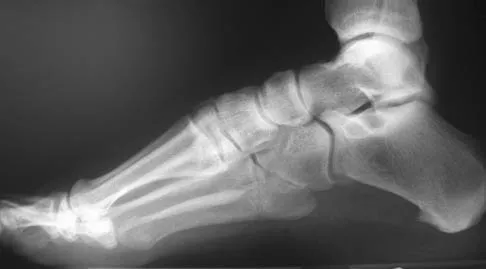

The condition shown in Figures 9a and 9b is most likely the result of

Explanation

The clinical photograph and radiograph show gout, which is the result of urate deposition in the joint and soft tissues. Radiographs frequently reveal periarticular erosions. The crystals are intracellular and negatively birefringent under the polarized microscope. Treatment for acute flares include colchicines, indomethacin, and corticosteroids (including injections). Medications such as allopurinol help prevent recurrent flares. Tophi such as that seen in this patient are often confused with and associated with infection. Wortmann RL, Kelley WM: Crystal-induced inflammation: Gout and hyperuricemia, in Harris ED, Budd RC, Firestein GS, et al (eds): Kelley's Textbook of Rheumatology, ed 7. New York, NY, Elsevier Science, 2005, pp 1402-1429. Trumble TE (ed): Hand Surgery Update 3: Hand, Elbow, & Shoulder. Rosemont, IL, American Society for Surgery of the Hand, 2003, pp 433-457.